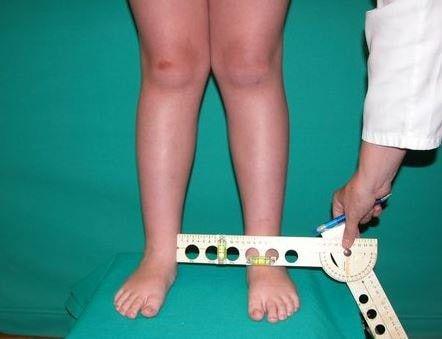

دسامبر 21, 2020زانوی ضربدری یا پای ضربدری وضعیتی ست که در آن زانوها روبهداخل تمایل دارند.

هنگامی که پاها در حالتی صاف قرار میگیرند، زاویهی روبهداخل دارند و به هم میچسبند اما قوزک پاها با فاصلهی زیادی از هم قرار میگیرند.

در اصطلاح پزشکی زانوی ضربدری، ژنووالگوم نام دارد. این وضعیت دردناک و ظاهری ناخوشایند دارد و میتواند منجر به آرتروز زودهنگام زانو شود.

اکثر کودکانی که دچار زانوی ضربدری هستند، خودبهخود مشکلشان برطرف میشود اما اگر شدت زانو و پای ضربدری بیشتر شود و تا سن ۱۰ سالگی بهبود نیابد، به ارزیابی و آزمایشهای بیشتری نیاز است

یکی از علائم زانو و پای ضربدری این است که هنگامیکه زانوها را کنار یکدیگر قرار میدهند، قوزک پاها بافاصلهی بسیار زیادی از هم قرار میگیرند.

تشخیص

ژنووالگوم معمولاً وقتی در سنین بسیار پایین بروز کند در مراحل اولیه تشخیص داده نمیشود. در کودکان و بزرگسالان، پزشک متخصص سعی در تشخیص علت بروز این مشکل میکند. اگر به هرگونه درمانی برای اصلاح این مشکل نیاز باشد باید ابتدا علت آن معین شود.

برای تشخیص دقیق زانو و پای پرانتزی، پزشک متخصص نیاز دارد دربارهی سابقهی پزشکی فرد را سؤالاتی را مطرح کند.

پزشک متخصص همچنین موارد زیر را مشاهده خواهد کرد:

- فرم زانوها در هنگام ایستادن

- نحوهی راه رفتن بیمار

- وجود تفاوت بیت طول پاها با یکدیگر

- پزشک ممکن است به دنبال یافتن الگوهای ناهمواری نیز در کفی کفشهای فرد باشد. در برخی موارد، پزشک برای بررسی ساختار استخوانها، انجام ام آر آی یا

- عکس رادیولوژی را توصیه کند.